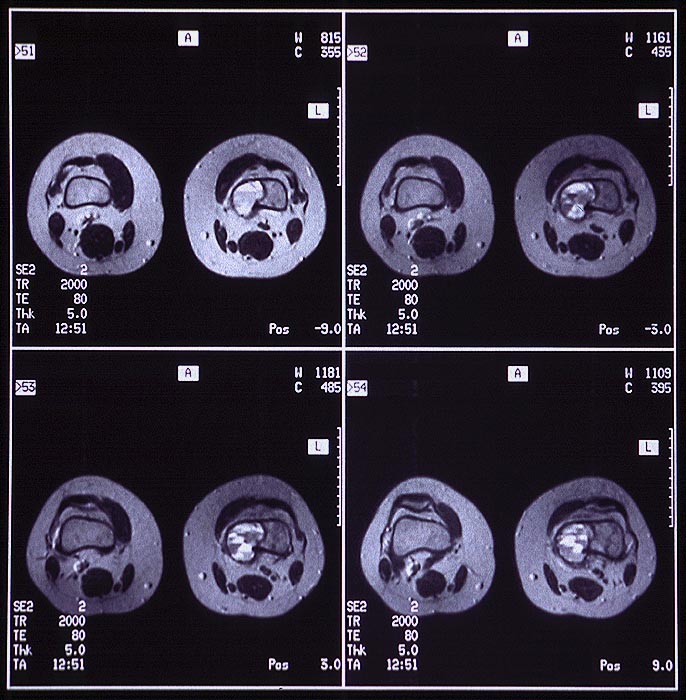

Aneurysmatische Knochenzyste

Knochen, Femur

MRT: In der distalen linken Femurmetaphyse medial eine exzentrisch gelegene mehrkammrige Zyste. Im Kernspintomogramm erkennt man bei starker T2-Gewichtung Flüssigkeitsspiegel.